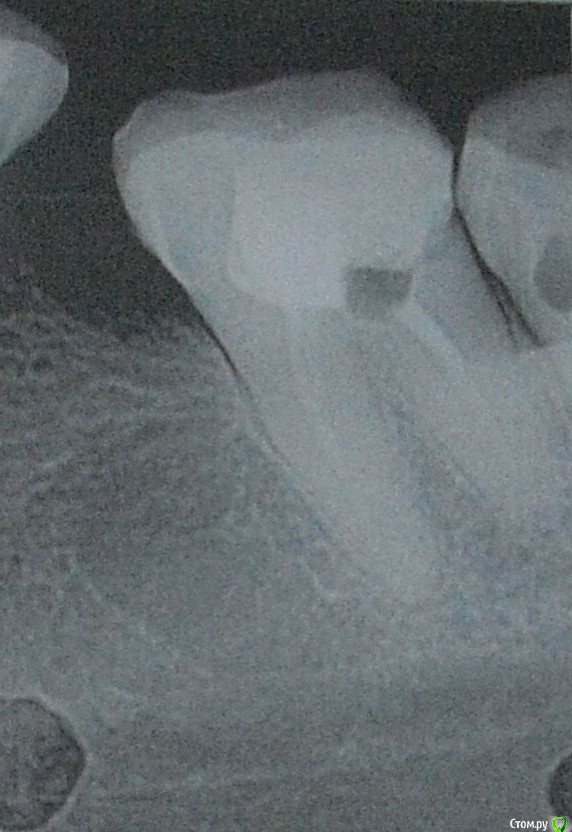

Здравствуйте! две недели назад был флюс.Хирург сделал надрез, дренаж не ставил, выписал антибиотики полоскание содой с солью. Отек сошел, но не полностью - десна немного увеличена. Все это время выходил гной. Дня три гной не выходит, но там белая фигня какая-то как налет, но как будто под кожей. Я не понимаю, т ли не долечили то ли что. Хирург говорит что нужно удалять 8 зуб что причина в кармане (это он определил по рентгену) и что иначе десна не пройдет. Но яне понимаю откуда там карман мне никогда туда пища то не забивалась. Поранить грубой щетиной щетки я реально могла но чтобы там остатки пищи гнии странно как-то.... на рентгене фото 1 это 7 зуб, а на фото 2 это  7 и 8 зуб. Зуб мудрости у меня не болит! Неужели без удаления никак? там действительно по рентгену карман? Подскажите пожалуйста уважаемые доктора! И еще момент хирург предлагает в качестве анастезии убистезин! говорит что он лучше обезболивает а так как идет воспалительный процесс то лидокаин с адреналином могут плохо подействовать и будет больно! Я постоянно принимаю анаприлин, он нормально сочетается с убистезином? раньше мне кололи лидокаин садреналином и я нормально переносила. Что скажете про убистезин, заранее большое спасибо!

post-58333-0-62010500-1565033843_thumb.jpg